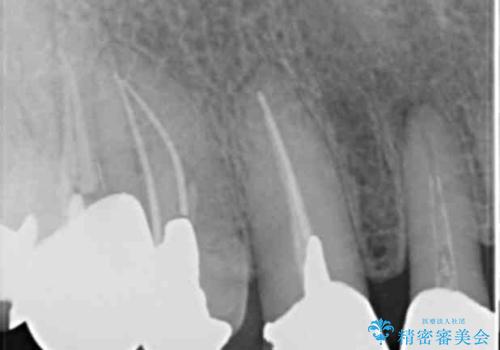

- 前歯のセラミック治療から4年半経過した患者様です。

4年半前のクラウン装着時と変わらず、まるで天然歯のように自然に見えました。

患者様の良好なセルフケアと精密な適合の良いクラウンにより、歯肉の腫脹や退縮も認められませんでした。

4年半前に行った治療に大変ご満足頂き、他の部位の治療のため再来院して下さいました。